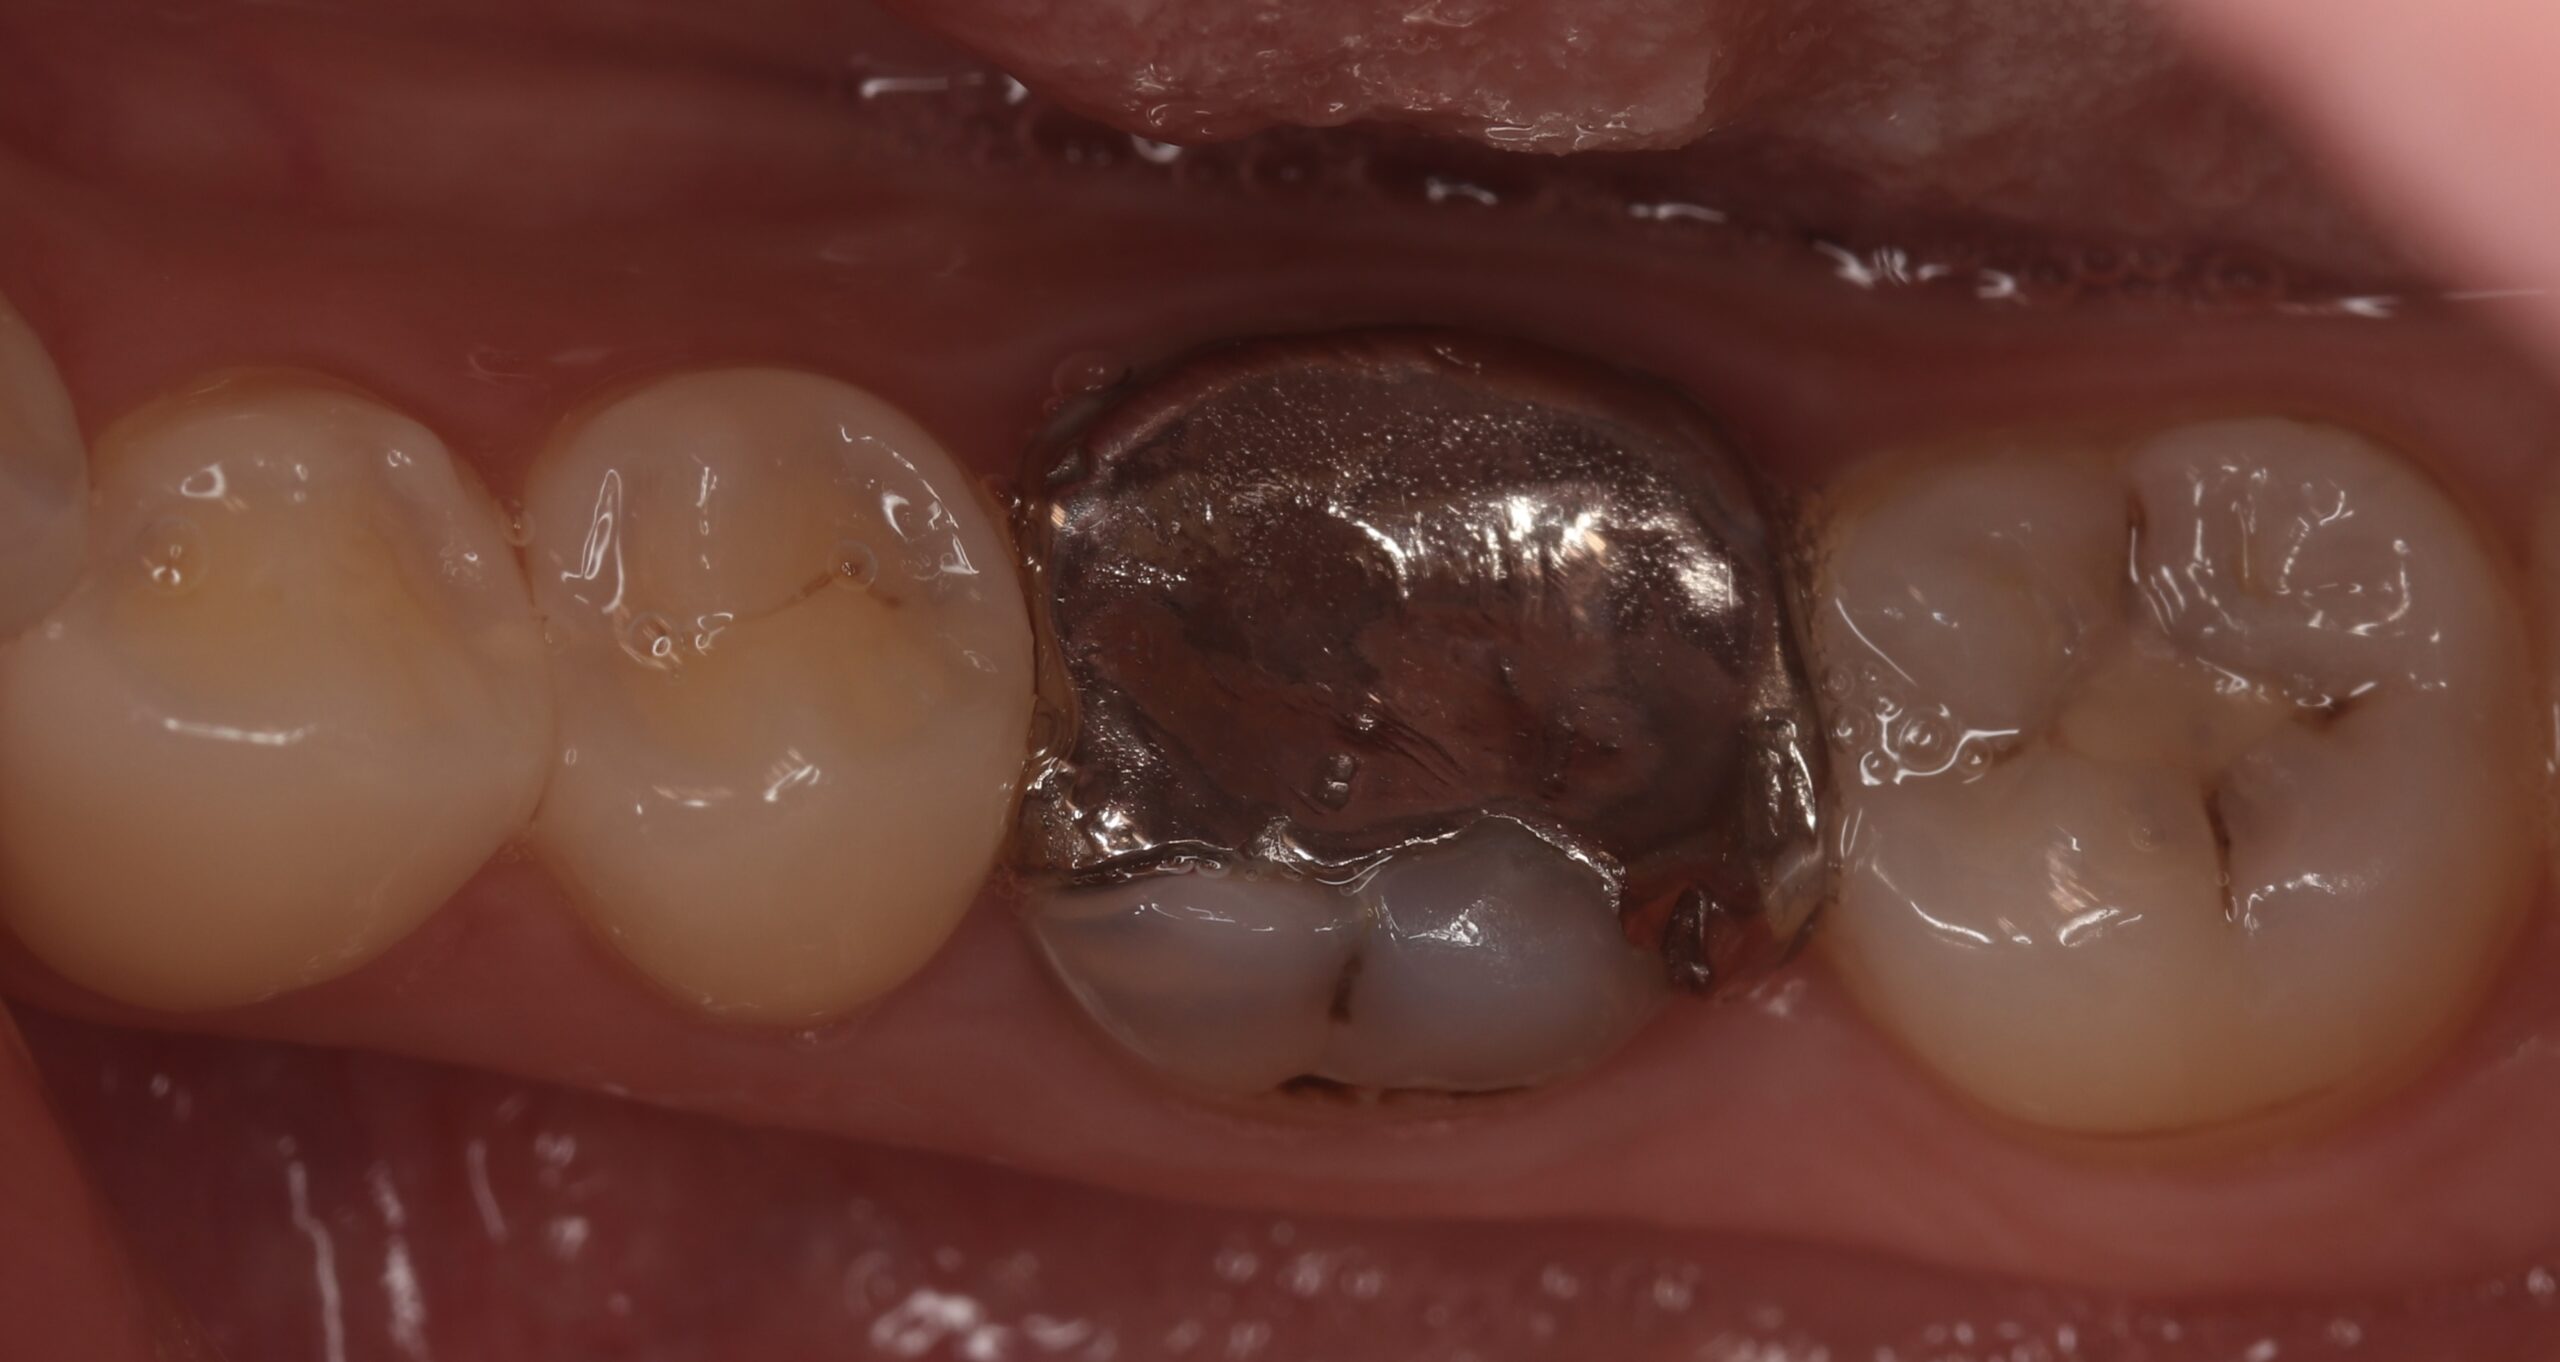

奥歯をジルコニアクラウンで治療した症例

BEFORE AFTER

| 主訴 | 噛むと痛い、銀歯のところを白く治したい |

| 治療内容 | 右下の奥歯の金属の被せものの周りからむし歯になっており、以前行われていた神経の治療(根管治療)を再度行った後、被せ物による修復を行いました。奥歯は噛む力が強くかかる部位であるため、高い強度を持つ「ジルコニアクラウン」を選択しました。金属を一切使用していないため、歯茎の黒ずみや金属アレルギーの心配がありません。 |